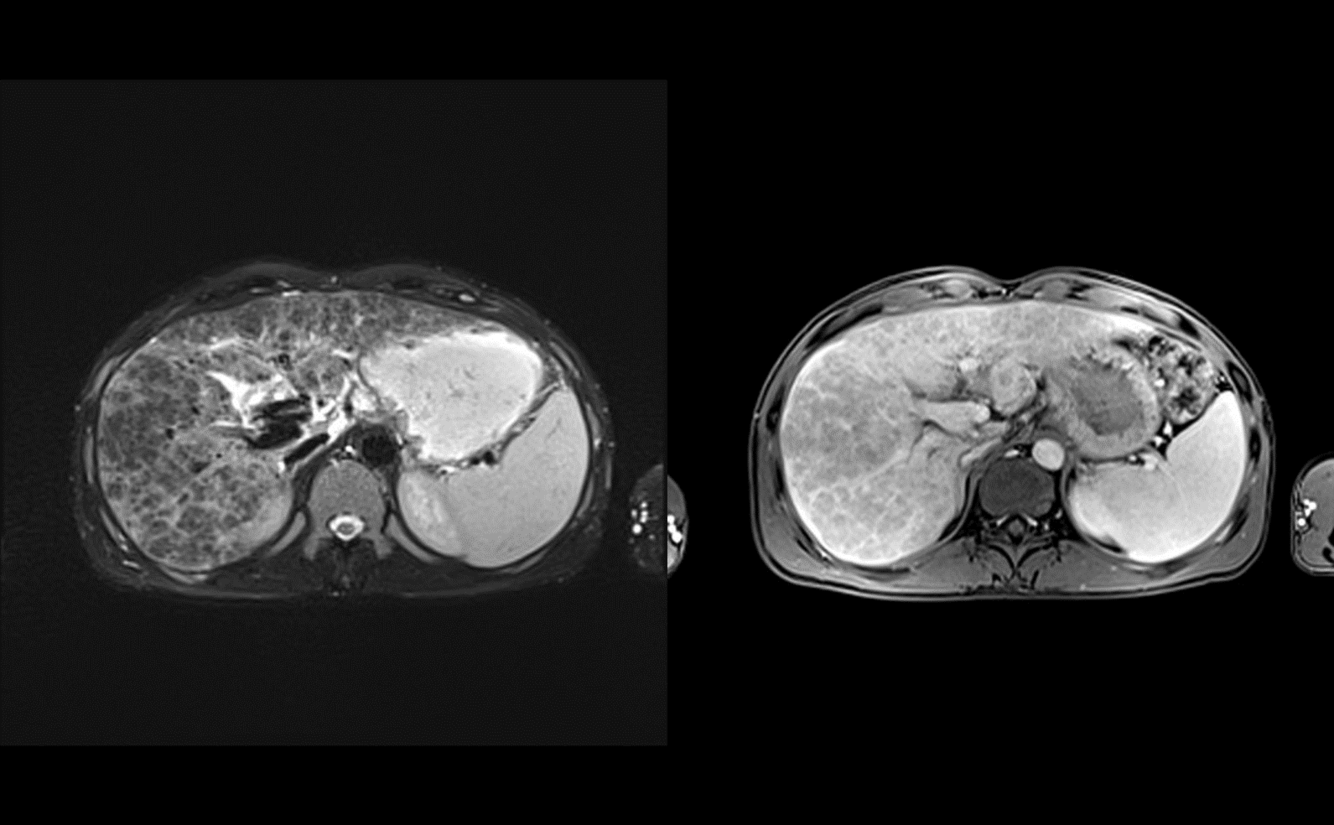

middle age woman with pruitis and fatigue

PBC

T2: if parenchymal lace-like fibrosis and periportal halo sign are seen together the sensitivity for PBC can approach 70%

Presentation: The typical patient is a middle-aged woman presenting with symptoms of fatigue and pruritus and laboratory test evidence of cholestasis.